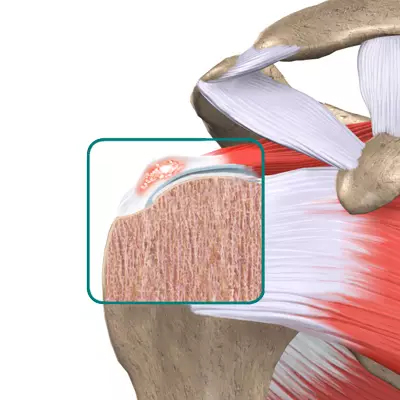

회전근개파열

어깨를 감싸고 있는 힘줄(극상건,극하건,견갑하건,소원건)을 회전근개라 말하며 나이가 들면서 근육이 약해지고 일상생활 중 무리하거나 다쳐서 손상되거나 끊어지는 현상을 말합니다. 어깨통증의 원인 중 90%를 차지하며 파열되면 자연치유되는 경우는 거의 없어서 봉합수술이 필요합니다.